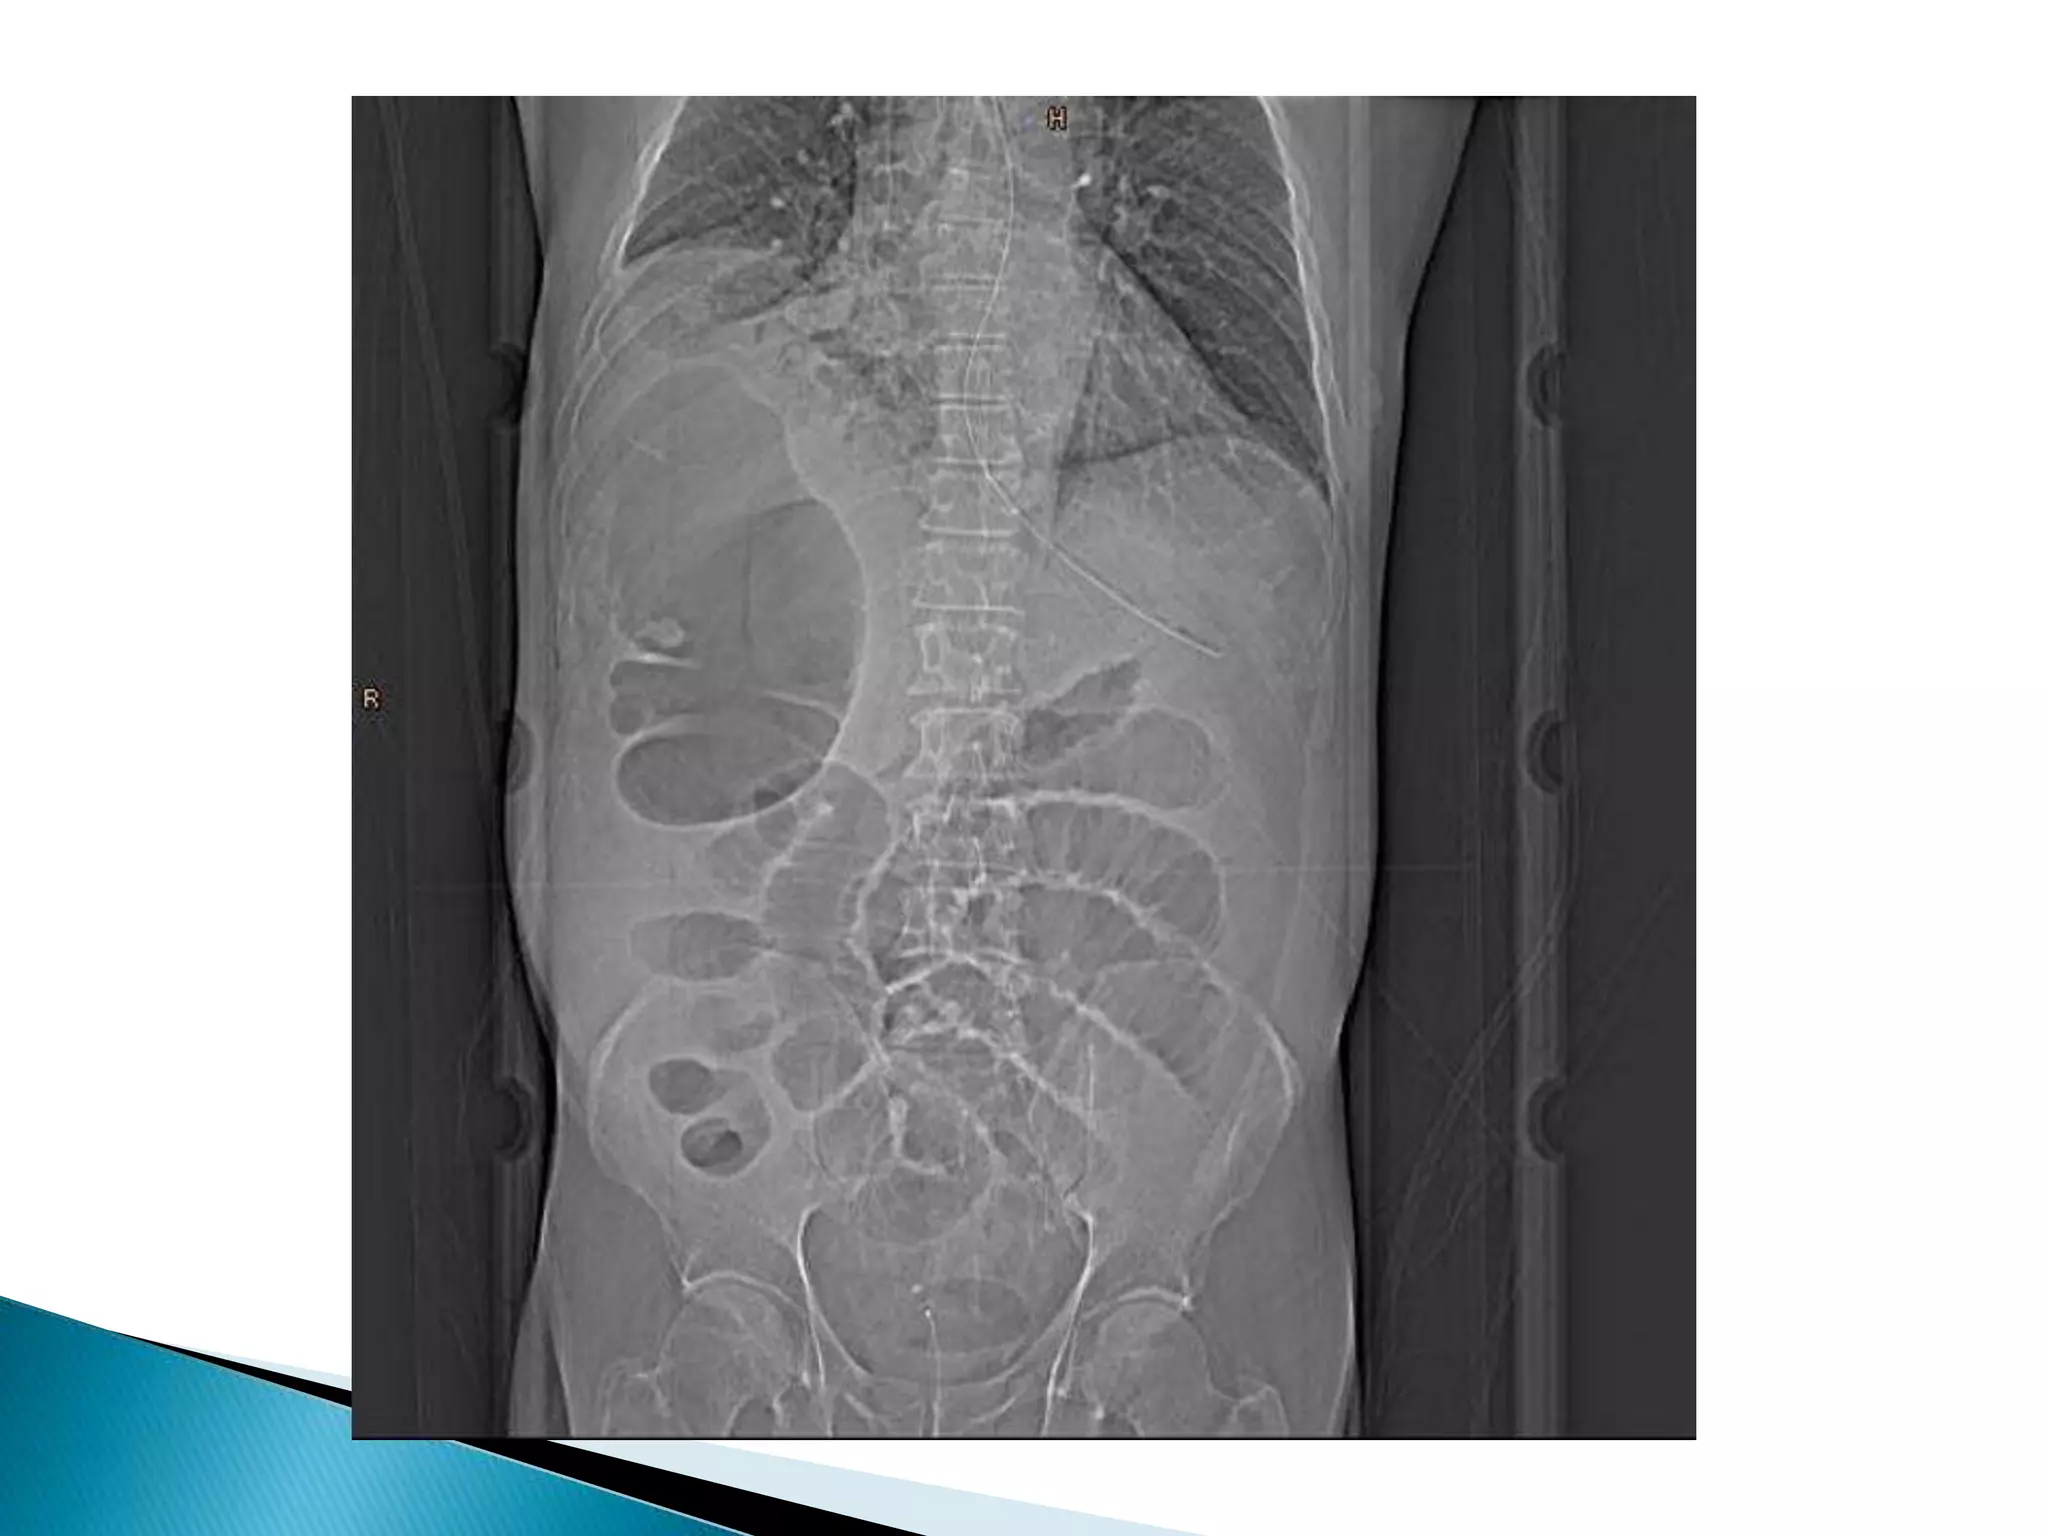

• Bowel looppoints to LUQ • Dilated cecum comes to rest in left upper quadrant • Bird’s-beak or bird-of-prey sign à seen on barium enema as it encounters the volvulated loop • CT scan useful in assessing mural wall ischemia

• Bowel loop points to LUQ

• Dilated cecum comes to rest in left upper

quadrant

• Bird’s-beak or bird-of-prey sign à seen on

barium enema as it encounters the volvulated

loop

• CT scan useful in assessing mural wall ischemia

Dilated cecum

Cecum

Contrast

In Descending colon

Barium Enema

Point of Obstruction

Ascending colon